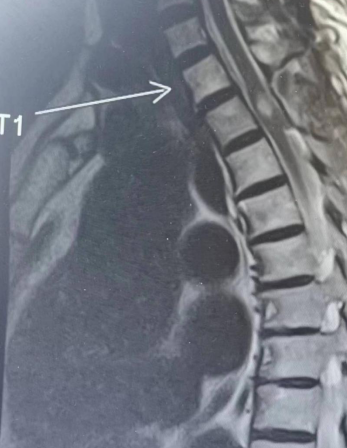

术后病人完全清醒,没有出现任何新的神经功能障碍,次日复查MR术野清晰干净,肿瘤切除干净。目前彭女士运动及感觉神经功能日渐恢复,病情恢复良好。

术后MR